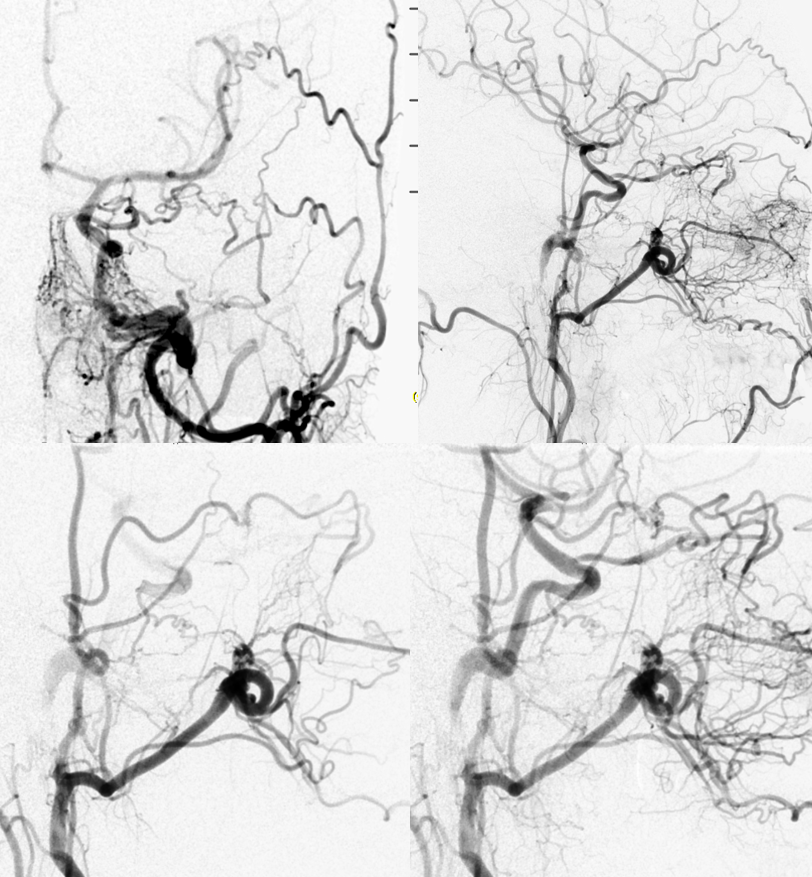

Odontoid arcade, Vidian artery, and other AP anastomoses

AP (above) and latearal (below) views of an ascending pharyngeal injection demonstrate a number of very instructive findings. The pharyngeal trunk (green) superior branch anastomoses wtih the ascending palatine artery (blue) and the vidian artery (yellow) which opaficies petrous ICA with a small blush (red). The neuromeningeal trunk (white) hypoglossal branch shows prominent ascending clival branches wich reconstitute the proximal cavernous carotid artery a the level of the MHT with another small carotid blush (red). The descending branch (green) of the hypoglossal division opacifies various components of the odontoid arch (black arrows). A prominent musculospinal branch (blue) reconstitutes the vertebral artery (pink).

Same case, with ICA injection with a prominent vidian artery( yellow), which is retrogradely opacified on the AP injection.

Ascending pharygeal to anterior spinal (purple) anastomosis via the odontoid arcade — for those who wish to embolize to vertebral and anterior spinal artery from the AP simultaneously, the way is through the odontoid arcade. This AP (originating directly from the internal carotid artery) opacifies the anterior spinal artery (purple) via the odontoid arcade (pink) which also demonstrates the vertebral artery (discontigous black). The C3 contribution to the anterior spinal artery is retrogradely opacified (blue). The nasal septal branches (light blue) are opacified via the superior pharyngeal artery connection to the sphenopalatine artery (yellow).